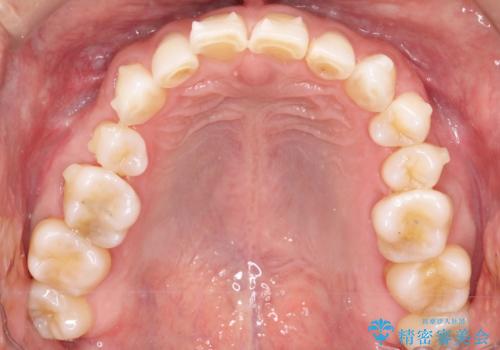

上の前歯の隙間とがたつきをインビザラインできれいな歯並びへ

- 以前矯正治療を他院にて行っており、最近上顎の隙間とガタガタが気になるとのことで来院されました。

上顎のみインビザラインにて矯正治療を行うこととなりました。